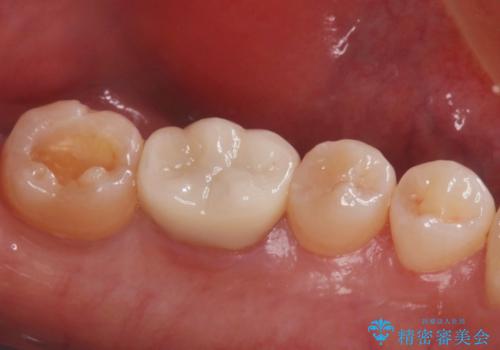

- 左下一番奥歯の詰め物が取れてしまったため治療を希望された患者様です。

詰め物が取れてしまったところは虫歯になっていたため、虫歯を綺麗に取り除いて詰め物にしていく治療計画を立てました。

詰め物の種類はセラミックインレーを希望されたため、セラミックにて治療をさせていただきました。